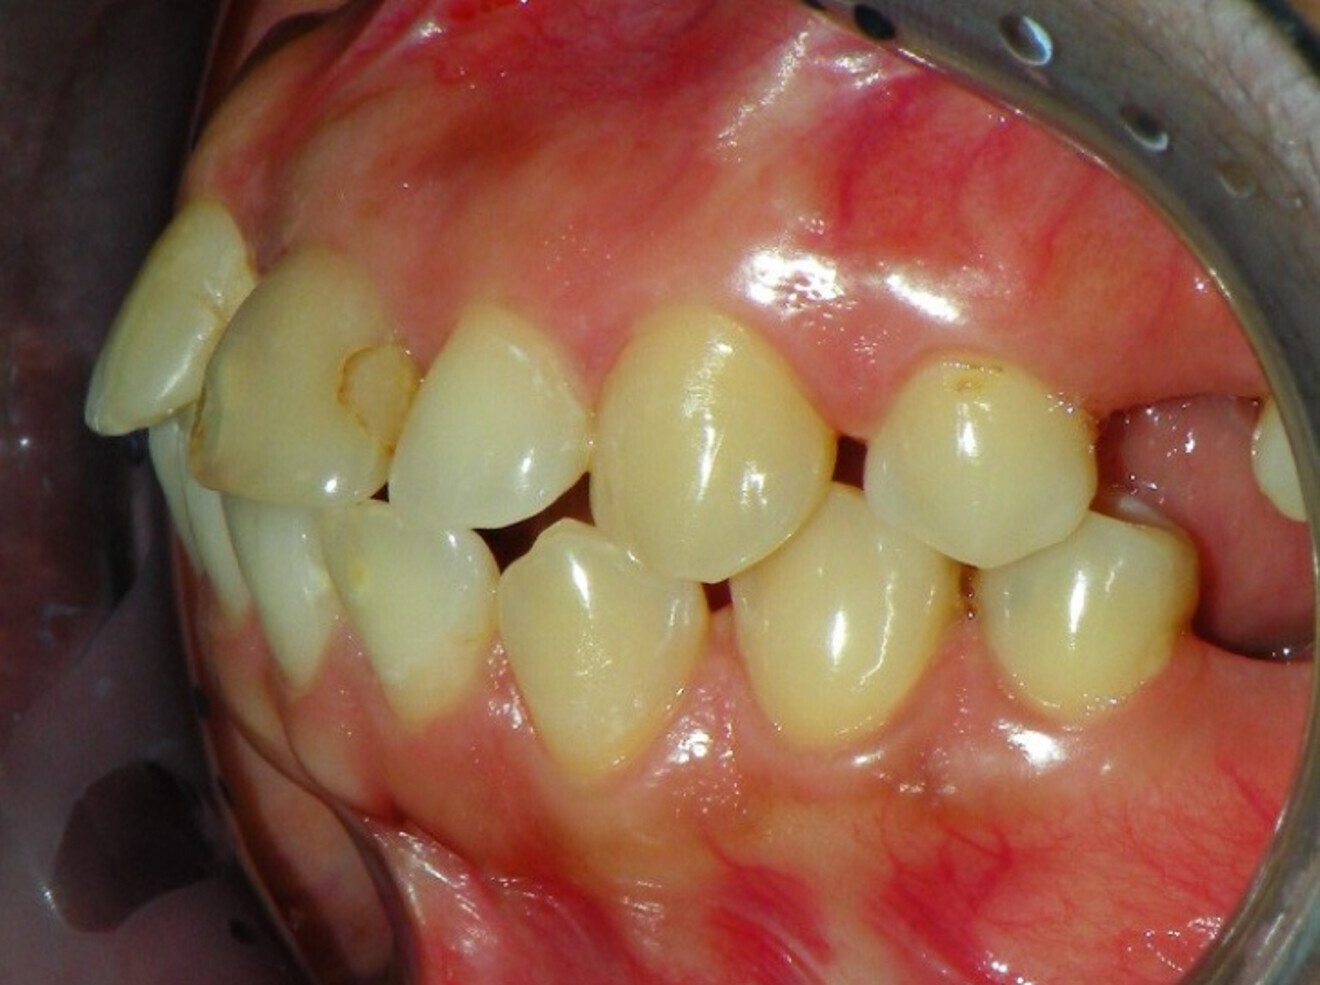

Intra-oral findings:

Class I malocclusion with poli diastemas in both upper and lower arch.

Overbite= 1mm Overjet = 3mm

No molar classification (absence of molars)

Class I canine on right and left side.

Upper midline (mesial to 11) on with face.

Lower midline on with the chin.